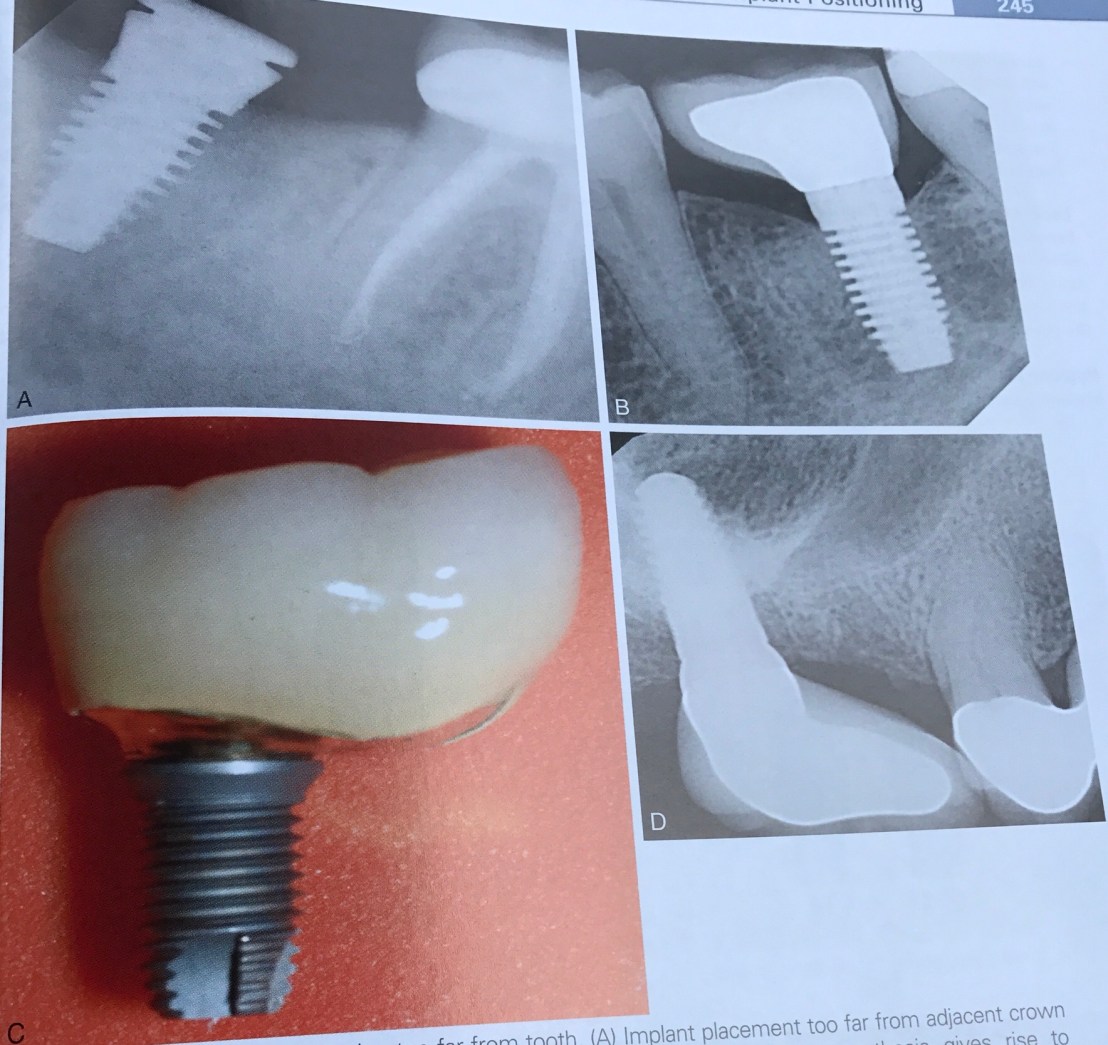

บทที่ 6 ความผิดพลาดจากการวางตำแหน่ง Implant

หรือพูดอีกอย่างคือ การวางตำแหน่งที่ถูกเหมือนการติดกระดุมเม็ดแรกถูกนั่นเองครับ สมมติถ้าเราวางตำแหน่งได้ไม่ถูก จะทำให้ต้อง compromise ตามมาทั้งในแง่ Pros, Perio และการคงอยู่ระยะยาวของ Implant เอง

นอกจากความใกล้กันเกิดแล้ว การวางตำแหน่งที่ห่างกันมากเกินไป ก็เกิดปัญหาได้ดังรูป

เกิดผล 2 อย่างคือ Overcontour ของ crown ทำให้เกิด Perio และ Occlusal table ที่ใหญ่ทำให้เกิด Cantilever ที่เกิดปัญหาทาง Pros และคนไข้จะ complain เรื่อง food impaction อยู่ตลอด

วิธีแก้ไข ถ้าอยู่ติดกับฟันธรรมชาติ คือ เรายอมให้เกิด Cantilever กับฟันธรรมชาติดีกว่าครับ โดยการสร้าง crown ให้ฟันธรรมชาติมี Occlusal table เพิ่มขึ้นแทน